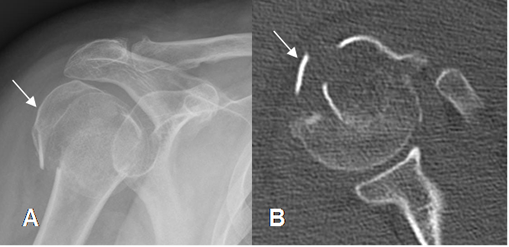

Fig 41. Fractura de la tuberosidad mayor.

A: Rx AP y B: TAC axial. Fractura conminuta y con desprendimiento de la tuberosidad mayor.